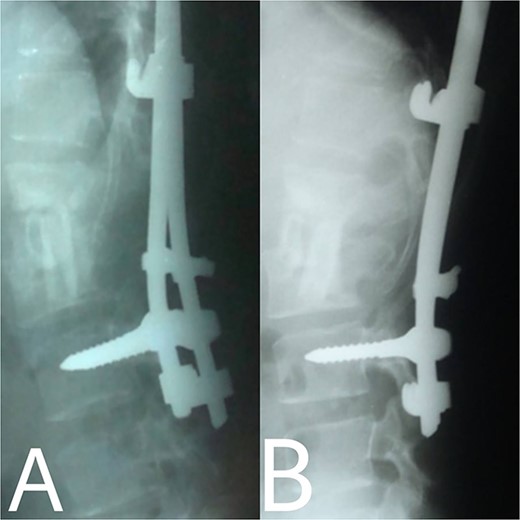

A 24-year-old farmer female was admitted to the Department of Neurosurgery with low back pain, no fever, cough, motor deficit, or any symptoms. Medical, surgical, family histories and physical examinations were unremarkable. The laboratory findings showed a white cell count of 9.8 × 103/μL, C-reactive protein concentrations of 20, erythrocyte sedimentation rate of 50 mm/1 h, 90 mm/2 h and tuberculin skin test was positive. X-ray films showed the collapse of the L1, L2 vertebrae, and L1–2 intervertebral space (Fig. 1). An abscess was observed at the L1–L2 vertebral level in lumbar magnetic resonance imaging (MRI) (Fig. 2). Chest X-rays and Sputum smear were negative. The patient was treated with anti-TB treatment (Isoniazid, Rifampicin, Ethambutol, Pyrazinamide) due to spinal TB findings on MRI (Fig. 3). After 40 days, the patient was diagnosed with grade 1/5 lower limb weakness, and bladder and bowel dysfunction, with no impairment in sensation, which predicts spinal infection. MRI confirmed these abnormalities and showed typical findings such as vertebral endplate destruction, bone marrow and disk signal abnormalities, and paravertebral or epidural abscesses (Fig. 3). Due to clinical manifestations and MRI spinal TB findings (Fig. 3), the patient underwent surgical debridement, interbody fusion and internal fixation with fibular autografting and supplemental posterior spinal stabilisation using a posterior-only approach. On post-operative follow-up, the treatment continued for 9 months, in addition to physical therapy for lower limb weakness. In the end, the patient returned to full motion with grade 5/5 in the lower limb, normal sensation, and no bladder or bowel incontinence. No recurrence was observed in the grafting area. Radiologically 2, 6 and 12 months, 14 years’ post-operation, the patient had achieved full bony graft spinal fusion (Figs 4–6).

(A, B) Post-operation, anteroposterior and lateral view showing fibular autograft implantation followed by supplemental posterior instrumentation.

(A, B) 2, 4 months after single-stage posterior extensive debridement and fibular autograft implantation followed by supplemental posterior instrumentation performed to treat the spinal infection.